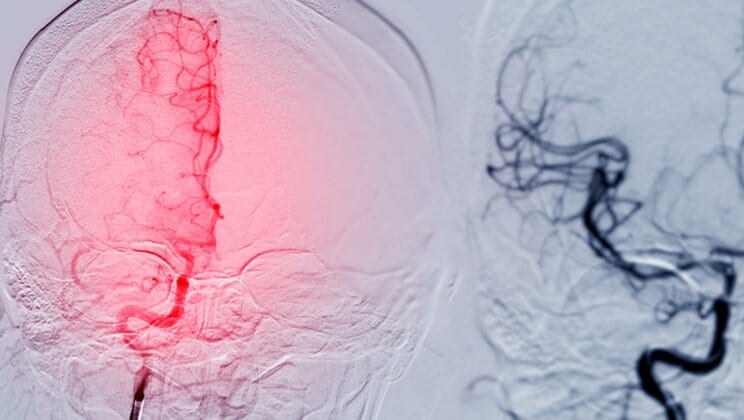

一つは、「心房細動」を背景とした「脳梗塞」を起こす可能性があることです。

「心房細動」とは、高齢者に多い心臓疾患の一つで、心臓の上部にある「心房」が規則正しく収縮・拡張せず、震えるように動いている状態のことです。

全身に血液を送りこむのは心臓の下部にある「心室」なので、心房が震えていても日常生活に大きな支障はありませんが、心房の中で血液が停滞して「血栓」ができやすくなります。

そして、カラオケで歌っている最中は、大きな声を出したり、力んだりすることで血圧が上昇します。すると、心房内で作られた血栓が遊離して、脳に向かう血管に詰まることがあるのです。